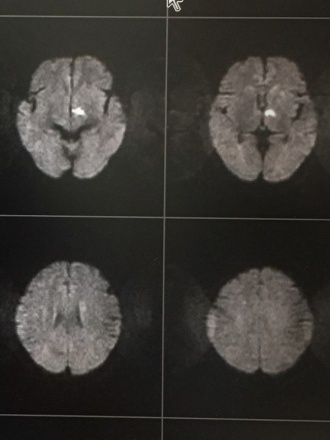

当院のMRI検査で新しい脳梗塞を認めました。脳卒中が原因の認知症であり、血管性認知症と言われています。

画像で白い部位が脳梗塞の場所で、視床(ししょう)という部位です。